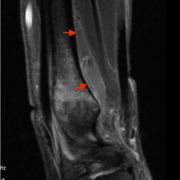

IRM normale  du Muscle Carré pronateur :

Masse charnue trapézoidale

En T2, chez 79 % des patients, hypersignal relatif par rapport aux muscles fléchisseurs ++

- différence moyenne de 16 %

- cet aspect prédomine sur le versant radial +

- phénomène d'angle magique

- orientation en sens opposé des fibres musculaires superficielles et profondes (2 chefs musculaires)

- diagnostic différentiel : atteinte du nerf interosseux antérieur, branche du nerf médian